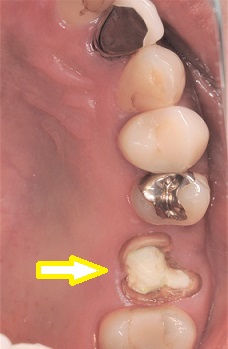

1,インプラント埋入前

右上奥歯が外れて他院で応急処置をされた後来院された患者様です。

インプラント治療を希望されたため、CT撮影を行ったところ、

インプラント埋入するうえで骨の厚みや幅に問題はありません。